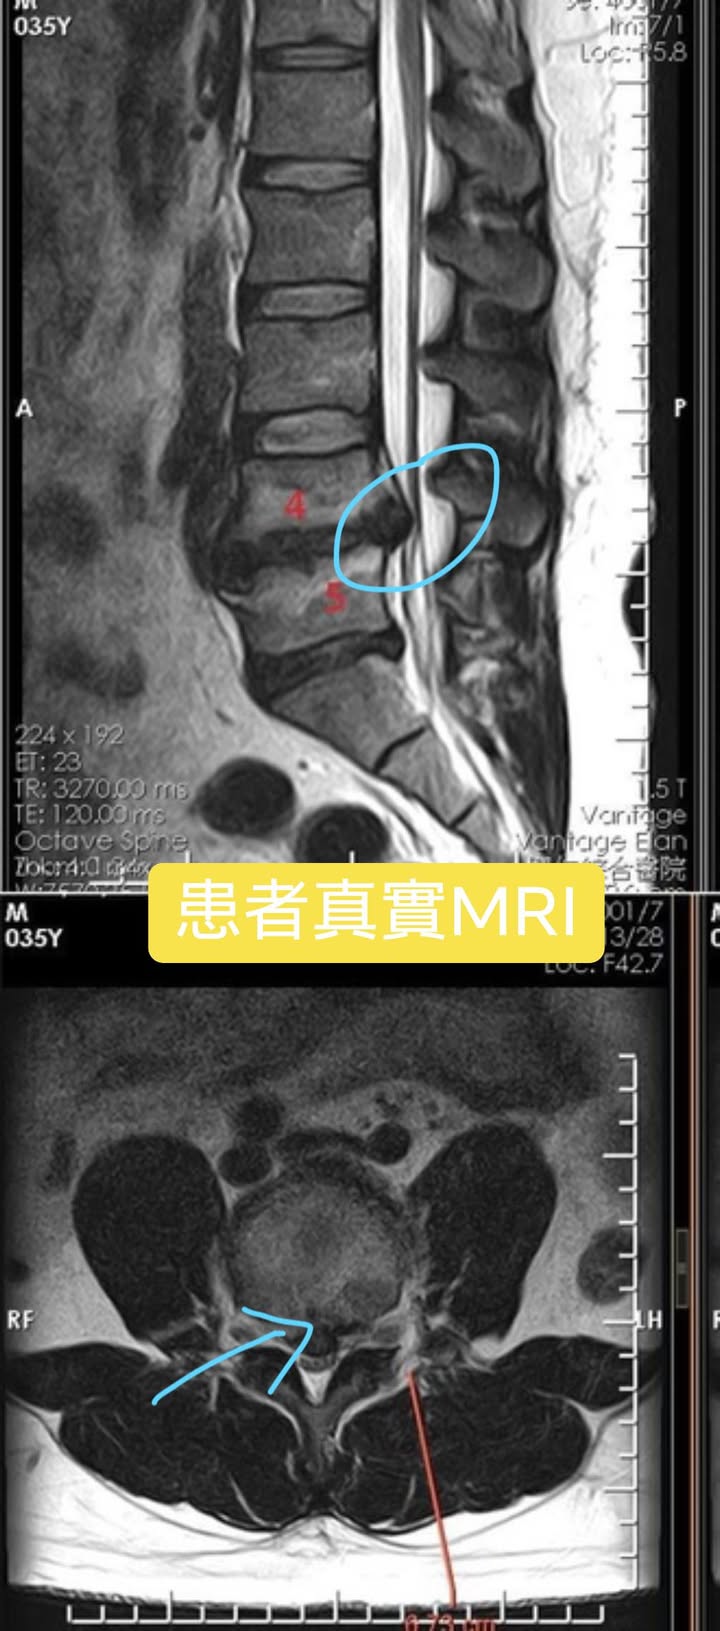

Cervical Spine Treatment Cases 腰椎治療案例 #巨大椎間盤突出醫案 #治療十二次提供前後MRI對比 #縱切面跟橫切面對比 #椎間盤突出為... 2021.09.03 ⭕️今天聽到患者說在某醫學中心開整段脊椎的刀 ,骨釘,骨水泥,人工椎間盤全上了,花... 2021.08.25 #典型下背手術失敗綜合症候群 #頸椎跟腰椎在短短幾年開了三次大刀 #腰椎融合固定支架... 2021.08.17 #馬尾神經症候群特殊醫案 #小便失禁合併下肢無力 #脊椎整合中醫微創逆轉勝 #脊刻救援... 2021.08.13 #骨刺髓核有可能吸收回去嗎?? #疼痛到無法行走的恐怖無法形容 #MRI核磁共振前後對比... 2021.08.14 #巨大椎間盤突出一定要開刀嗎? #兩家醫學中心外科醫師說很嚴重! #有沒有辦法逆轉勝... 2021.08.10 ❖ 椎間盤突出治療醫案 ❖晨起痛爆整個人無法工作心情沮喪 😂骨科醫師說復健如果沒效可... 2022.05.12 #天才年輕賽車手巨大椎間盤突出醫案 #八周治療完全逆轉勝康復 #重新回到合法賽車場競... 2021.07.20 #腰椎滑脫痛苦不堪 #右腳麻痛無法彎腰刷牙 #感謝桃園市楊小姐熱情見證 #患者親自贈送... 2021.06.15 #巨大椎間盤突出醫案 #真的逆轉勝超感動 #三個月治療完全徹底改善 #脊刻救援成功 #徹... 2021.06.12 ⭕️L4L5巨大椎間盤突出治療醫案 🌟八週之內解除危機逆轉成功 😁順利降級成功解封印 💪... 2021.07.08 #腰椎多節椎管狹窄治療醫案 #腎臟病患者可接受中醫微創筋膜療嗎? #感謝台北市信義區張... 2021.06.01 #腰椎手術失敗綜合症候群 #感謝桃園呂伯伯熱情見證 #何時必須優先考慮再次動刀 #脊刻... 2021.07.31 #感謝新店吳先生熱情見證 #車禍後導致椎間盤突出醫案 #傳統復健六周無效痛苦不堪 #脊... 2021.05.29 #椎間盤突出治療醫案 #破紀錄三週解決 #真的逆轉勝 #感謝新莊周先生熱情見證 #脊椎整... 2021.05.26 ← 上一頁 6 7 8 9 10 下一頁 →